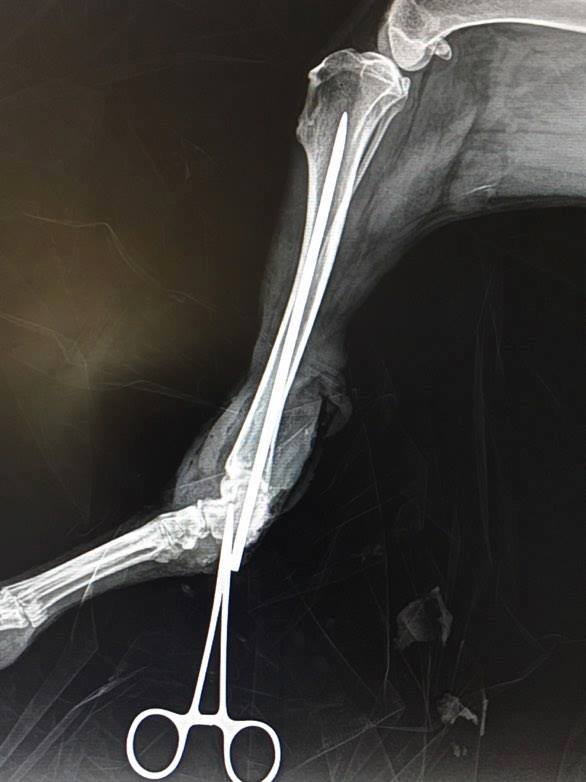

Šedou je po operaci. Jak se předpokládalo, nebyla to žádná sranda. Podařilo se pomocí šroubu ukotvit achilovku, S využitím kostního drátu upevnit patní kost. a kotvení, aby zůstal sval. Ale stále ještě není dostatek kůže, aby se dalo všechno zakrýt. Teď zaklepu. Patní kost je značně špatná, mohlo by dojít k zánětu a tím i k rozpadu.Tak, snad vydrží a začne prorůstat s drátem, tím by bylo vyhráno. Pokud se tohle nepodaří, pořád by hrozilo to nejhorší - amputace. Vzhledem k nedostatku kůže se bude tlapka ještě mockrát převazovat. .No snad jsem to popsala trochu srozumitelně a lajcky. Po dohodě s MVDr. LAPÁČKEM si ji na klinice nechají až do zítra, aby mohli ihned medikamentosně zasáhnout v případě otoků a i mohli Šedou ulevit od bolesti. Dám zase vědět, jak budeme pokračovat. Pan doktor Vám poslal pár fotek z operace. Z celého srdce panu doktorovi LAPÁČKOVI a jeho týmu děkuji. A všem děkuji za zájem a podporu.